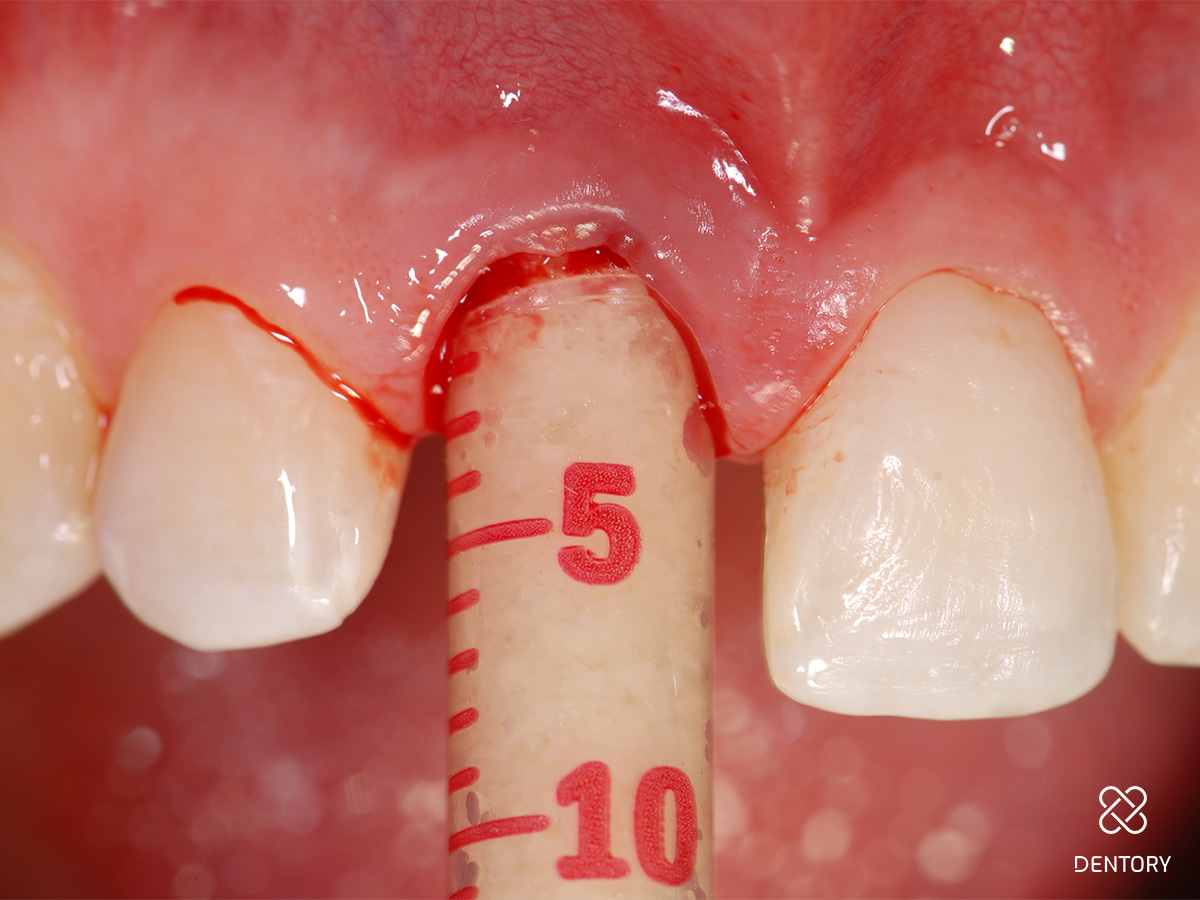

Abbildung 5

Sondieren der bukkalen Knochenstrukturen mittels Biotyp-Sonde; im Bereich der Resorption kam es zum lokalen Verlust der vestibulären Lamelle.